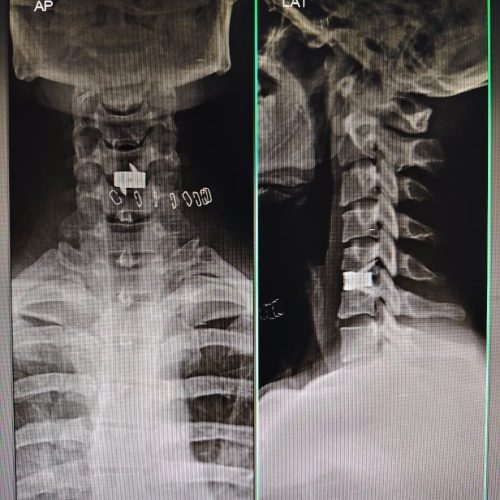

• Anterior Cervical Discectomy and Fusion (ACDF): ACDF is a surgical procedure performed on the cervical spine to remove a damaged or herniated disc that’s pressing on the spinal cord or nerve roots. The term anterior refers to the front of the neck, where the surgeon accesses the spine through a small incision. After the problematic disc is removed, the empty disc space is filled with an implant and the adjacent vertebrae are fused together for stability.

This procedure helps relieve neck and arm pain, restore nerve function, and prevent further spinal degeneration.

anterior cervical discectomy and fusion surgery